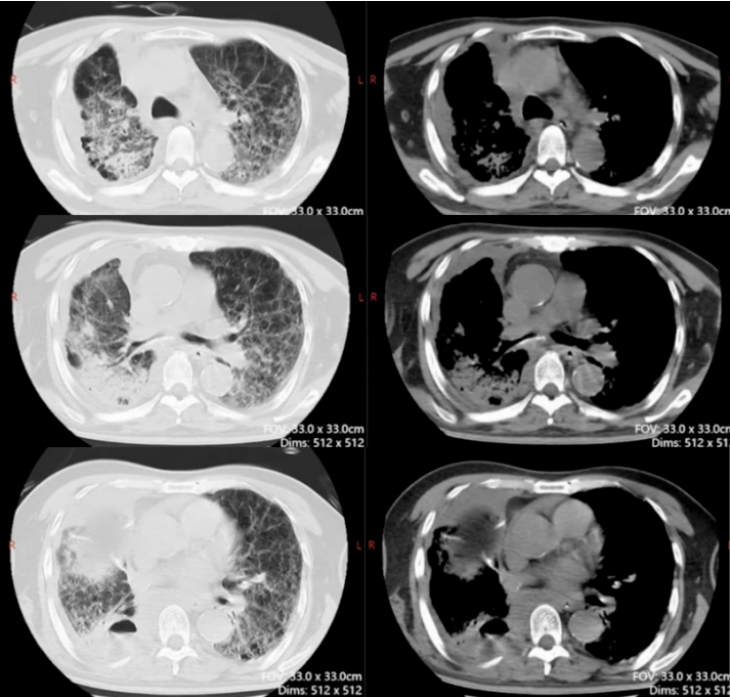

5. 影像学

2021年5月19日(外院手术治疗前),患者胸部CT示:右下肺占位性病变(图1)。术后病理分期提示为腺鳞癌。

图1 患者外院胸部CT(2021-05-19)

2021年8月26日复查胸部CT提示复发,右下肺病灶较5月进一步增大(图2)。10月12日再次复查胸部CT,右下肺病灶仍清晰可见(图3)。

图2 患者外院胸部CT(2021-08-26)

图3 患者外院胸部CT(2021-10-12)